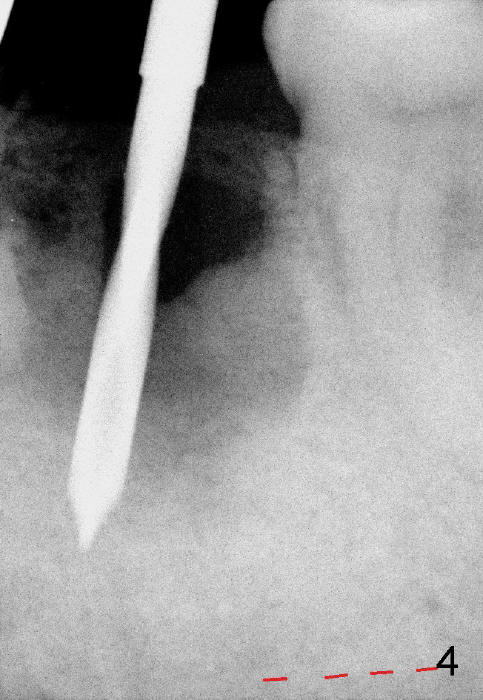

A 84-year-old man has severe pain distal to #18 (Fig.1). The affected tooth is planned to be restored by a 7x17 mm implant (Fig.2).